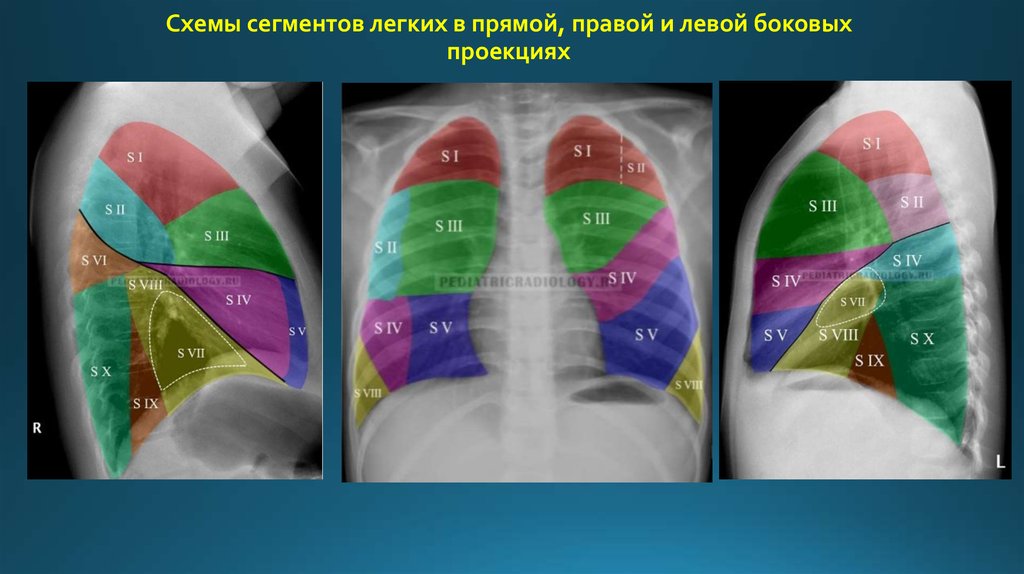

Анатомические изображения сегментов легких различных животных

Раздел: Другие животные